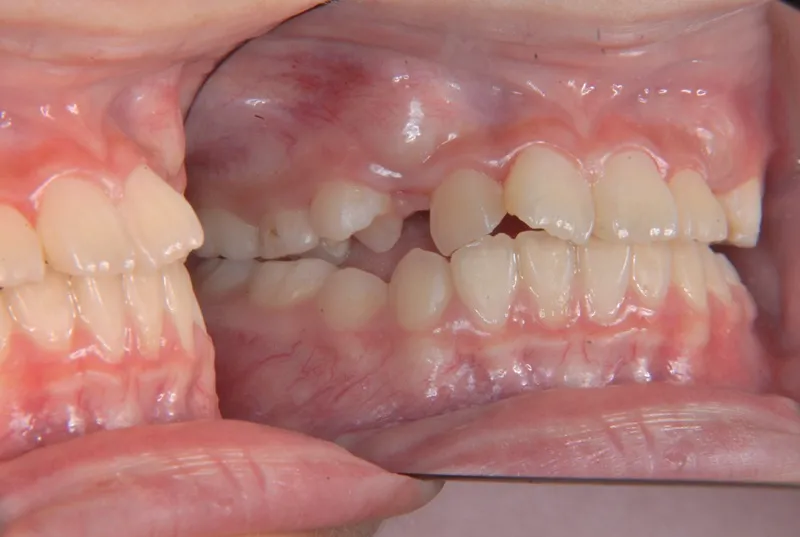

治療終了後

治療回数35回、5年9ヶ月の治療期間で矯正治療を終了しました。